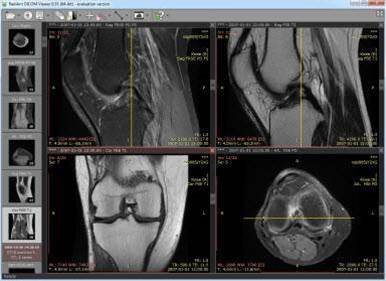

This uses transmission control protocol (TCP) ports 104 and 11112, often in clear text over the internet, and the researchers were able to use a DICOM viewer application to access the data.

Some of the systems provided DICOM web-based image viewers as well.